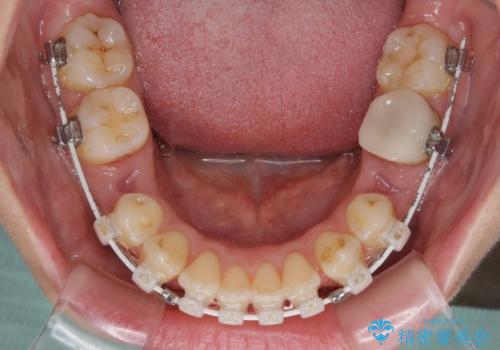

- 矯正装置

- 審美装置

- 治療計画

- 上の前歯の飛び出した感じを改善したいとのことで来院された患者様です。

上顎左右第一小臼歯2本、下顎左右第二小臼歯2本を抜歯し、ワイヤー装置にて口元を引っ込めるよう矯正治療を行うこととしました。

上下の前歯に隙間が空くほど上顎前歯が前に飛び出していましたが、抜歯矯正により上下前歯がぴったりと付くほど口元を引っ込めることができました。